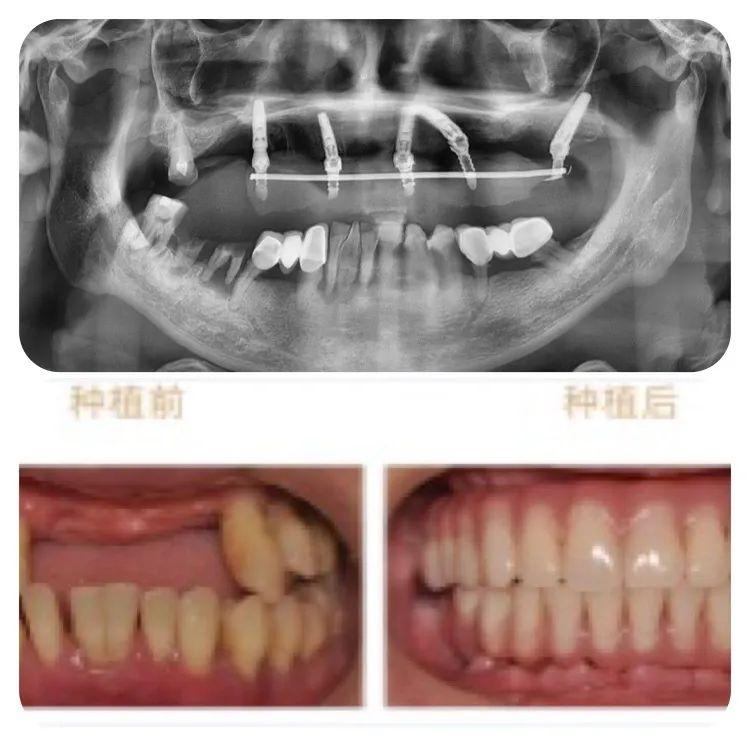

此次成功種牙的78歲高齡的老人,不但同時(shí)患有高血壓、心臟病及糖尿病,口腔條件也不容樂(lè)觀:因外傷引起牙缺失2年,有較嚴(yán)重的牙周炎,是典型的高齡疑難種牙案例。

診療方案

針對(duì)老人的口腔條件,重慶泰康拜博口腔VIP種植工作室通過(guò)3D數(shù)字化種植設(shè)計(jì)系統(tǒng)為他個(gè)性化計(jì)了帶1顆穿翼板種植的負(fù)重種植牙方案,即拔即種,全口牙在1天之內(nèi)完成了種牙、戴冠全過(guò)程,手術(shù)完成后帶上臨時(shí)牙冠,牙齒就已經(jīng)可以正常使用。

術(shù)后恢復(fù)

術(shù)后1周復(fù)查,通過(guò)口腔CT檢查,可以看見(jiàn)老人的種植牙、穩(wěn)固。老人自己也描述,他在種牙的時(shí)候感覺(jué)輕松快速,幾乎沒(méi)有痛感,打個(gè)盹的功夫,牙齒就種好了。